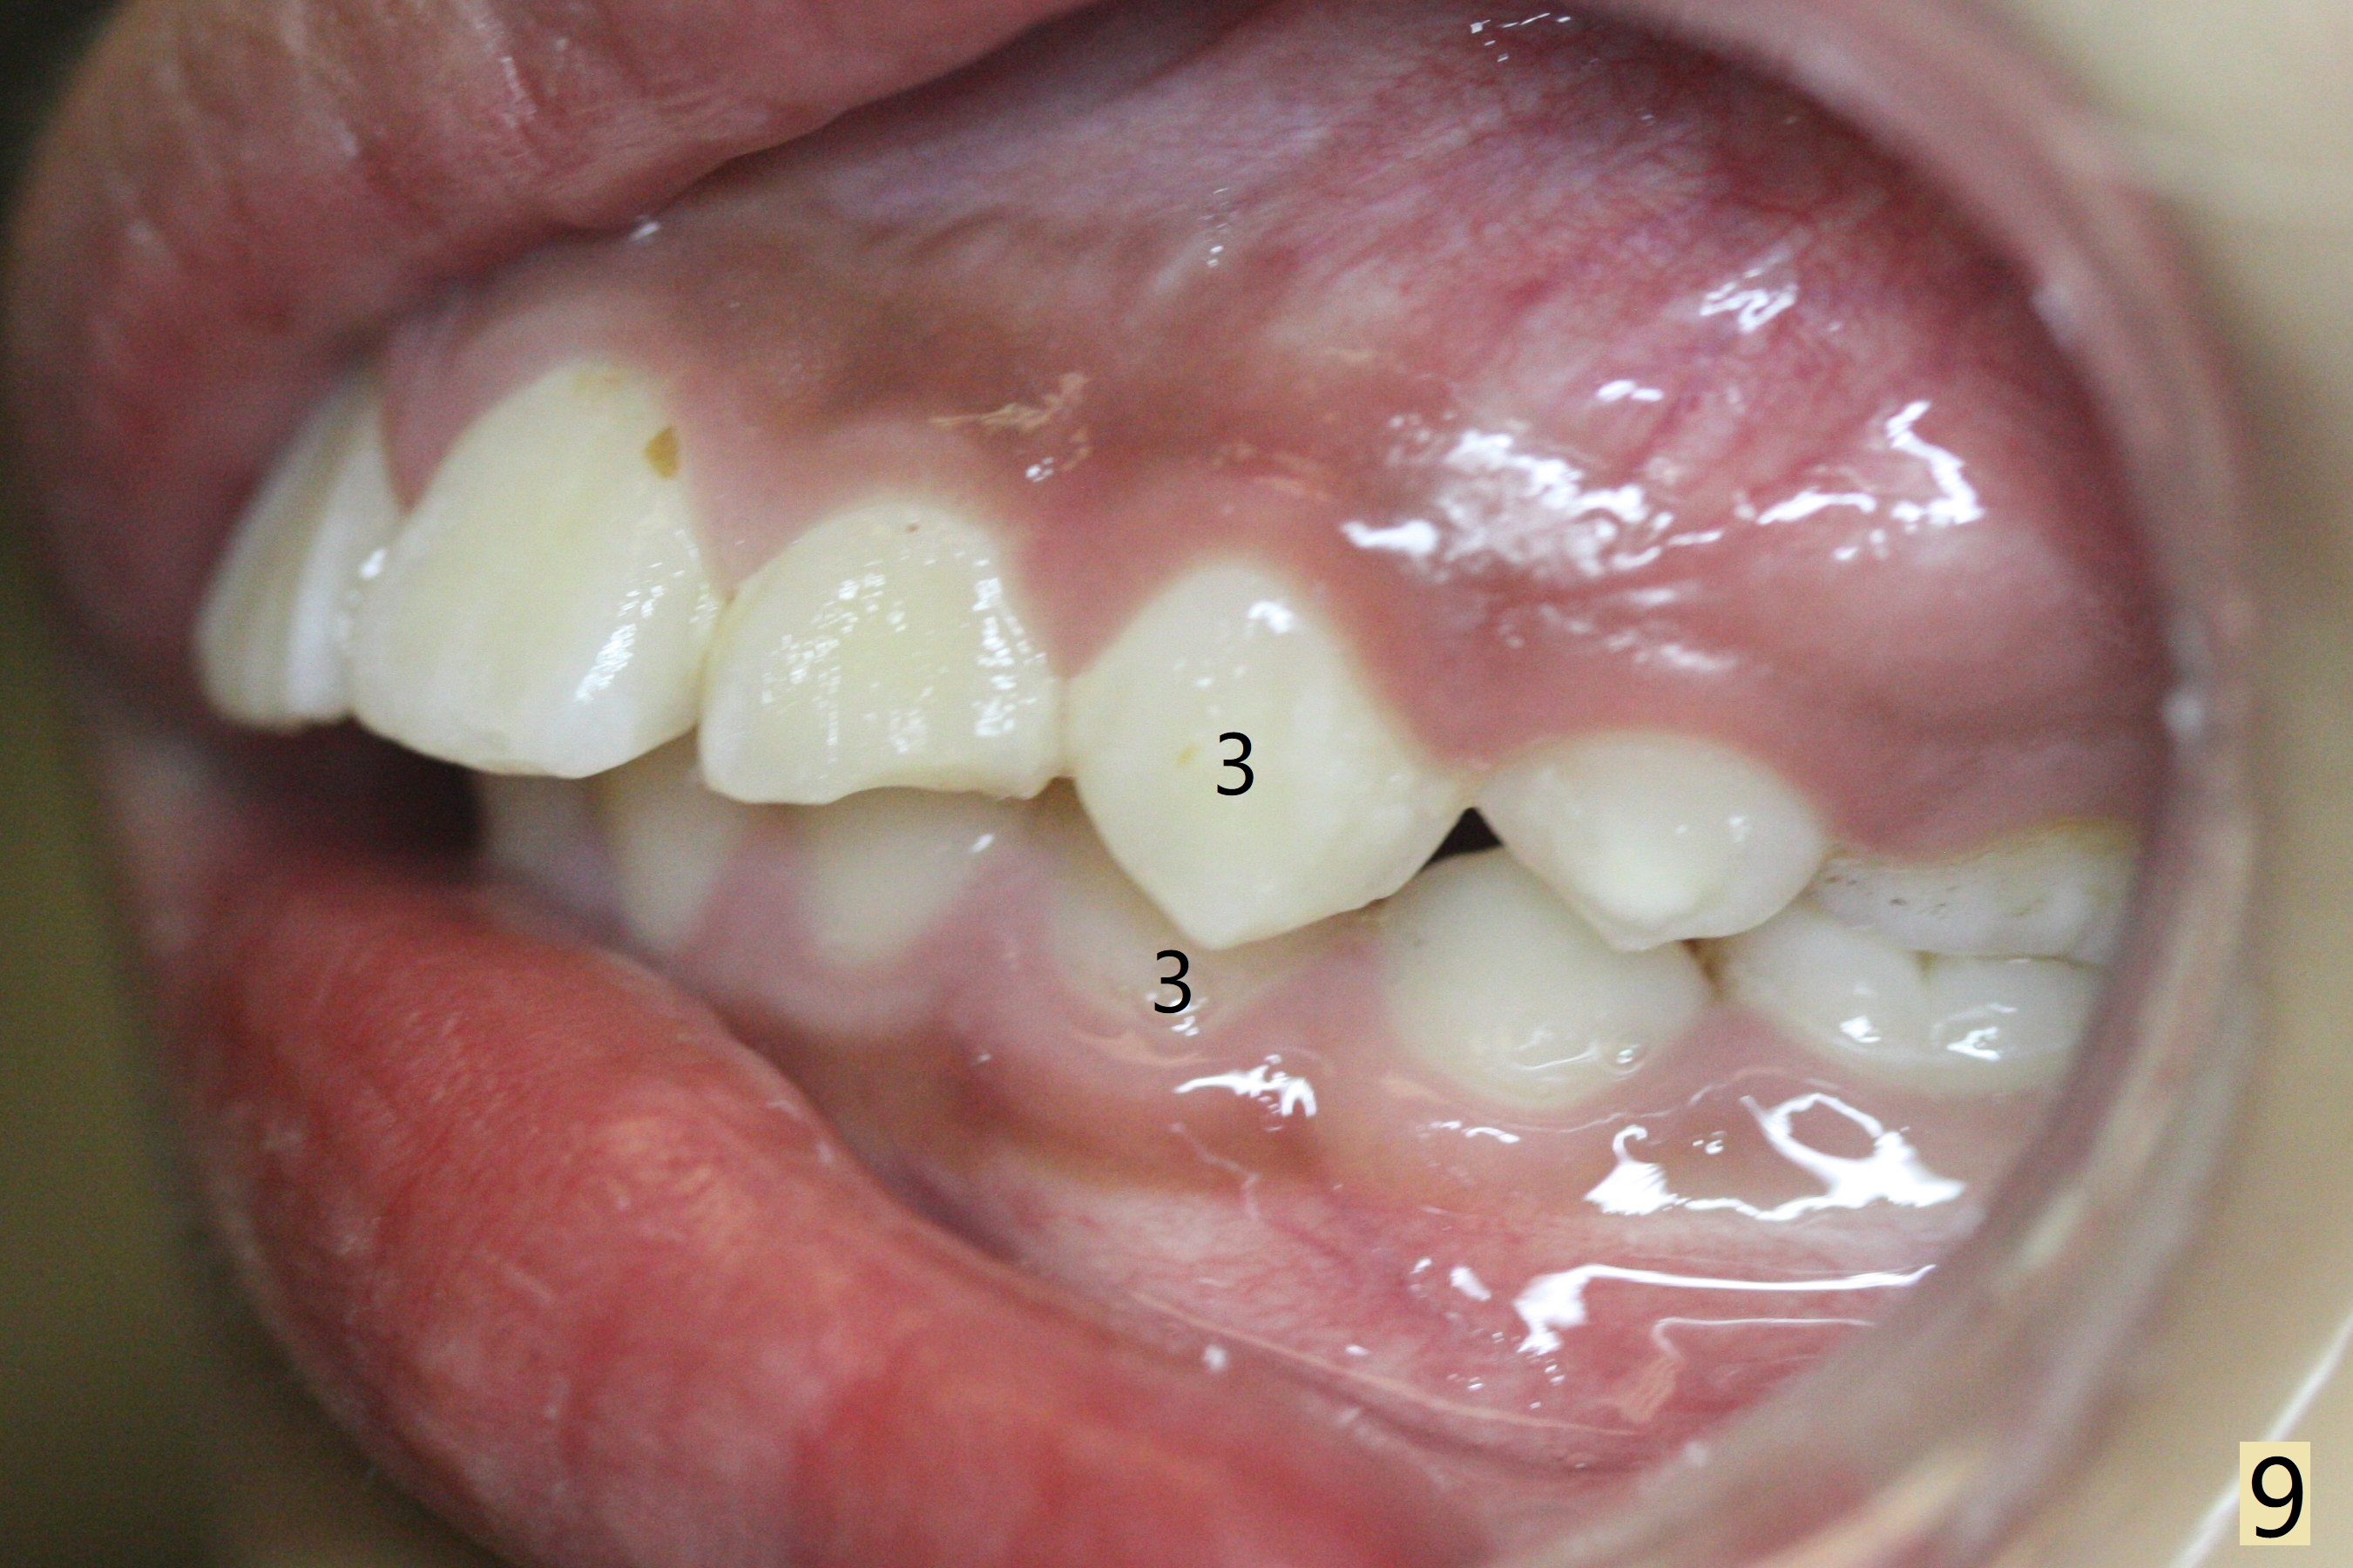

The mother of a 10-year-7-month old man requests treatment for the crowding lower incisors (Fig.14). The canines and molars are Class II by a half of a tooth (Fig.7,9,10,12). The dentition is mixed with E retention (Fig.13,14,16). Orthodontic treatment will start before E exfoliation for alignment and establishment of Class I occlusion as much as possible by distalizing U6s. Fine adjustment for intedigitation will be made when E exfoliate.